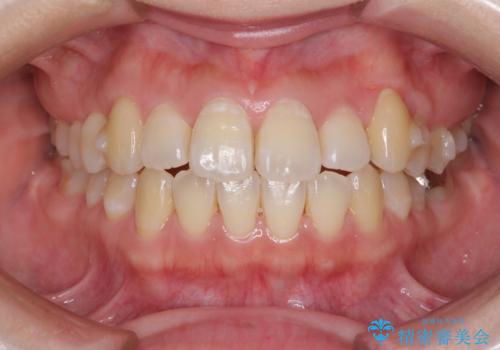

- 前歯がデコボコした上に口元が閉じにくいことを気にして来院された患者様です。

IPR(歯と歯の間を削る)と側方拡大では口の閉じにくさは改善できそうになく、一方で抜歯矯正を行うほどの突出感は認められませんでした。

親知らずを全て抜去し、歯列全体を後方に移動させることで口元の閉じにくさいを改善していくこととしました。

インビザラインでの歯列全体の後方移動は時間がかかりますが、しっかりと装着時間を守っていただいたので、スッキリとした口元に仕上げることができました。